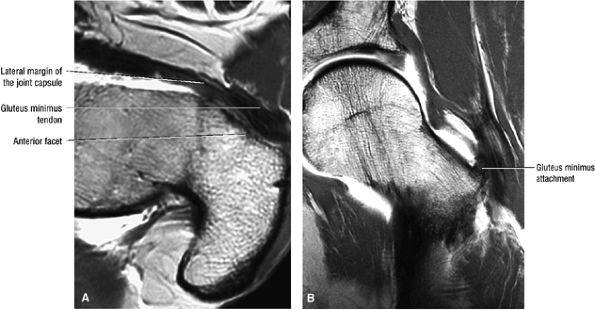

FIGURE 3.17 ● GLUTEUS MINUMUS The gluteus minimus abducts and medially rotates the thigh when the extremity is extended.

FIGURE 3.30 ● Normal sagittal anatomy of the hip. (A and B) On medial sagittal images, the course of the obturator internus, piriformis, and the adductor muscles can be followed and analyzed for strain injury or tears. (C and D) Tendinosis and tears of the common hamstring tendon origin on the ischial tuberosity are optimally viewed at this location and are extremely common in middle aged and elderly patients. (E and F) Although thinning and fraying of the articular cartilage can occur anywhere in the joint, chondral degeneration is most commonly seen first in the anterior superior quadrant, often accompanied by anterior labral tears, subchondral edema, and cystic change in the anterior acetabulum. When any one of these findings is present, a careful search for the others should be performed. (G and H) Linear tears of the anterior labrum can be mimicked by fluid filling a normal recess between the anterior labrum and the anterior joint capsule. Imaging in the axial and coronal planes is used to distinguish between a true tear and the normal recess, since a tear is visualized and confirmed in the axial and coronal planes, whereas a recess is only seen prominently in the sagittal plane. (K and L) The gluteus medius and minimus tendons have been referred to as the “rotator cuff” of the hip. The gluteus medius tendon inserts posteriorly on the greater trochanter, and the gluteus minimus tendon inserts anterolaterally on the greater trochanter. (I and J) Loose bodies commonly lodge in the joint recesses anterior and posterior to the femoral neck (deep to the iliofemoral and ischiofemoral ligaments). They are commonly seen (particularly in the sagittal plane) in patients with chondral degeneration. (M and N) Acute tears of the gluteus medius and minimus often mimic symptoms of a proximal femoral fracture. Chronic partial tears and tendinosis are frequently associated with trochanteric bursitis, and are common in middle-aged and elderly patients.